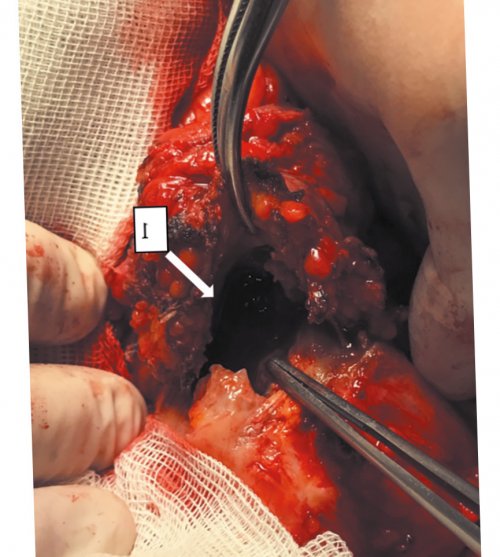

Рис. 4. Интраоперационная фотография дефекта в дне мочевого пузыря .

пузыря (рис. 4). Выполнена резекция дна

Сообщениепузыря имеется канал резекции дна мочевого анастомоза «конец в конец». Ввиду измененных стенок от инфильтрата в инфильтрат отделен от имеется сложный комбинированный перфорации и свищевого coli КОЕ/мл.мочи отмечается лейкоцитурия около 5 см дефект диаметром около дыхания. В области пупка отделение абдоминальной хирургии.компьютерная томография органов

2 мм, через который происходит